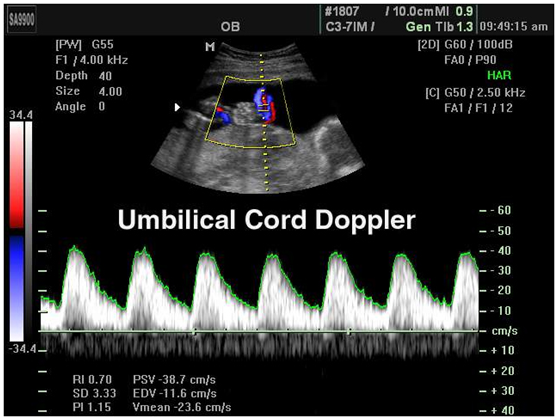

தொப்புள்தமனிடாப்ளர்ஸ்கேன் (Umbilical artery Doppler scan):

தொப்புள் தமனி டாப்ளர்ஸ்கேனில், குழந்தையிலிருந்து தொப்புள்கொடி வழியாக நஞ்சுக்கொடியை நோக்கி செல்லும் இரத்த ஓட்டம் சரிபார்க்கப்படுகிறது. குழந்தைக்குத்தேவையான அனைத்தையும் தாயின் நஞ்சுக்கொடியிலிருந்து பெறுகிறதா என்பதை உறுதிப்படுத்த இந்த ஸ்கேன் உதவுகிறது.தொப்புள் தமனிடாப்ளர்ஸ்கேன், தாய் ஒன்றுக்கு மேற்பட்ட குழந்தைகளை சுமந்து கொண்டிருந்தாலோ அல்லது கர்ப்பகாலத்தில் குழந்தையின் வளர்ச்சி விகிதம் குறைவாக இருந்தாலோ அல்லது குழந்தை ரீசஸ் (Rhesus) ஆன்டிபாடிகளால் பாதிக்கப்பட்டாலோ செய்யப்படுகிறது.